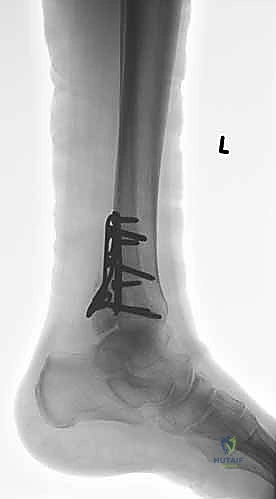

المرحلة الثالثة: رد العظام وتثبيت الكعب الوحشي (الشظية)

يبدأ الجراح عادة بإصلاح الشظية لأنها تعتبر "العمود الفقري" لاستقرار الكاحل. يتم إرجاع قطع العظم إلى مكانها التشريحي الطبيعي (الرد المفتوح). ثم يتم تثبيتها باستخدام شريحة معدنية (Plate) ومجموعة من المسامير (Screws) لتثبيتها بقوة.

المرحلة الرابعة: تثبيت الكعب الإنسي (الظنبوب)

بعد استقرار الجانب الخارجي، ينتقل الجراح للجانب الداخلي. يتم تنظيف منطقة الكسر من أي أنسجة محشورة، ثم يتم رد الكعب الإنسي وتثبيته غالباً باستخدام مسمارين طويلين (Cancellous screws) أو تقنية الأسلاك والشد (Tension band wiring) حسب شكل الكسر.

هنا تبرز خبرة أفضل طبيب عظام في صنعاء واليمن. يستخدم الدكتور هطيف جهاز الأشعة التلفزيونية داخل العمليات (C-arm) للتأكد من وضعية المسامير والشرائح. وفي حالات معينة، قد يستخدم المنظار المفصلي (Arthroscopy 4K) لفحص سطح الغضروف من الداخل والتأكد من خلوه من أي شظايا عظمية صغيرة.

أخيراً، يتم إغلاق الجروح باستخدام خيوط تجميلية دقيقة لتقليل الندبات، ويوضع الكاحل في جبيرة خلفية أو حذاء طبي واقي لحمايته خلال الأيام الأولى.